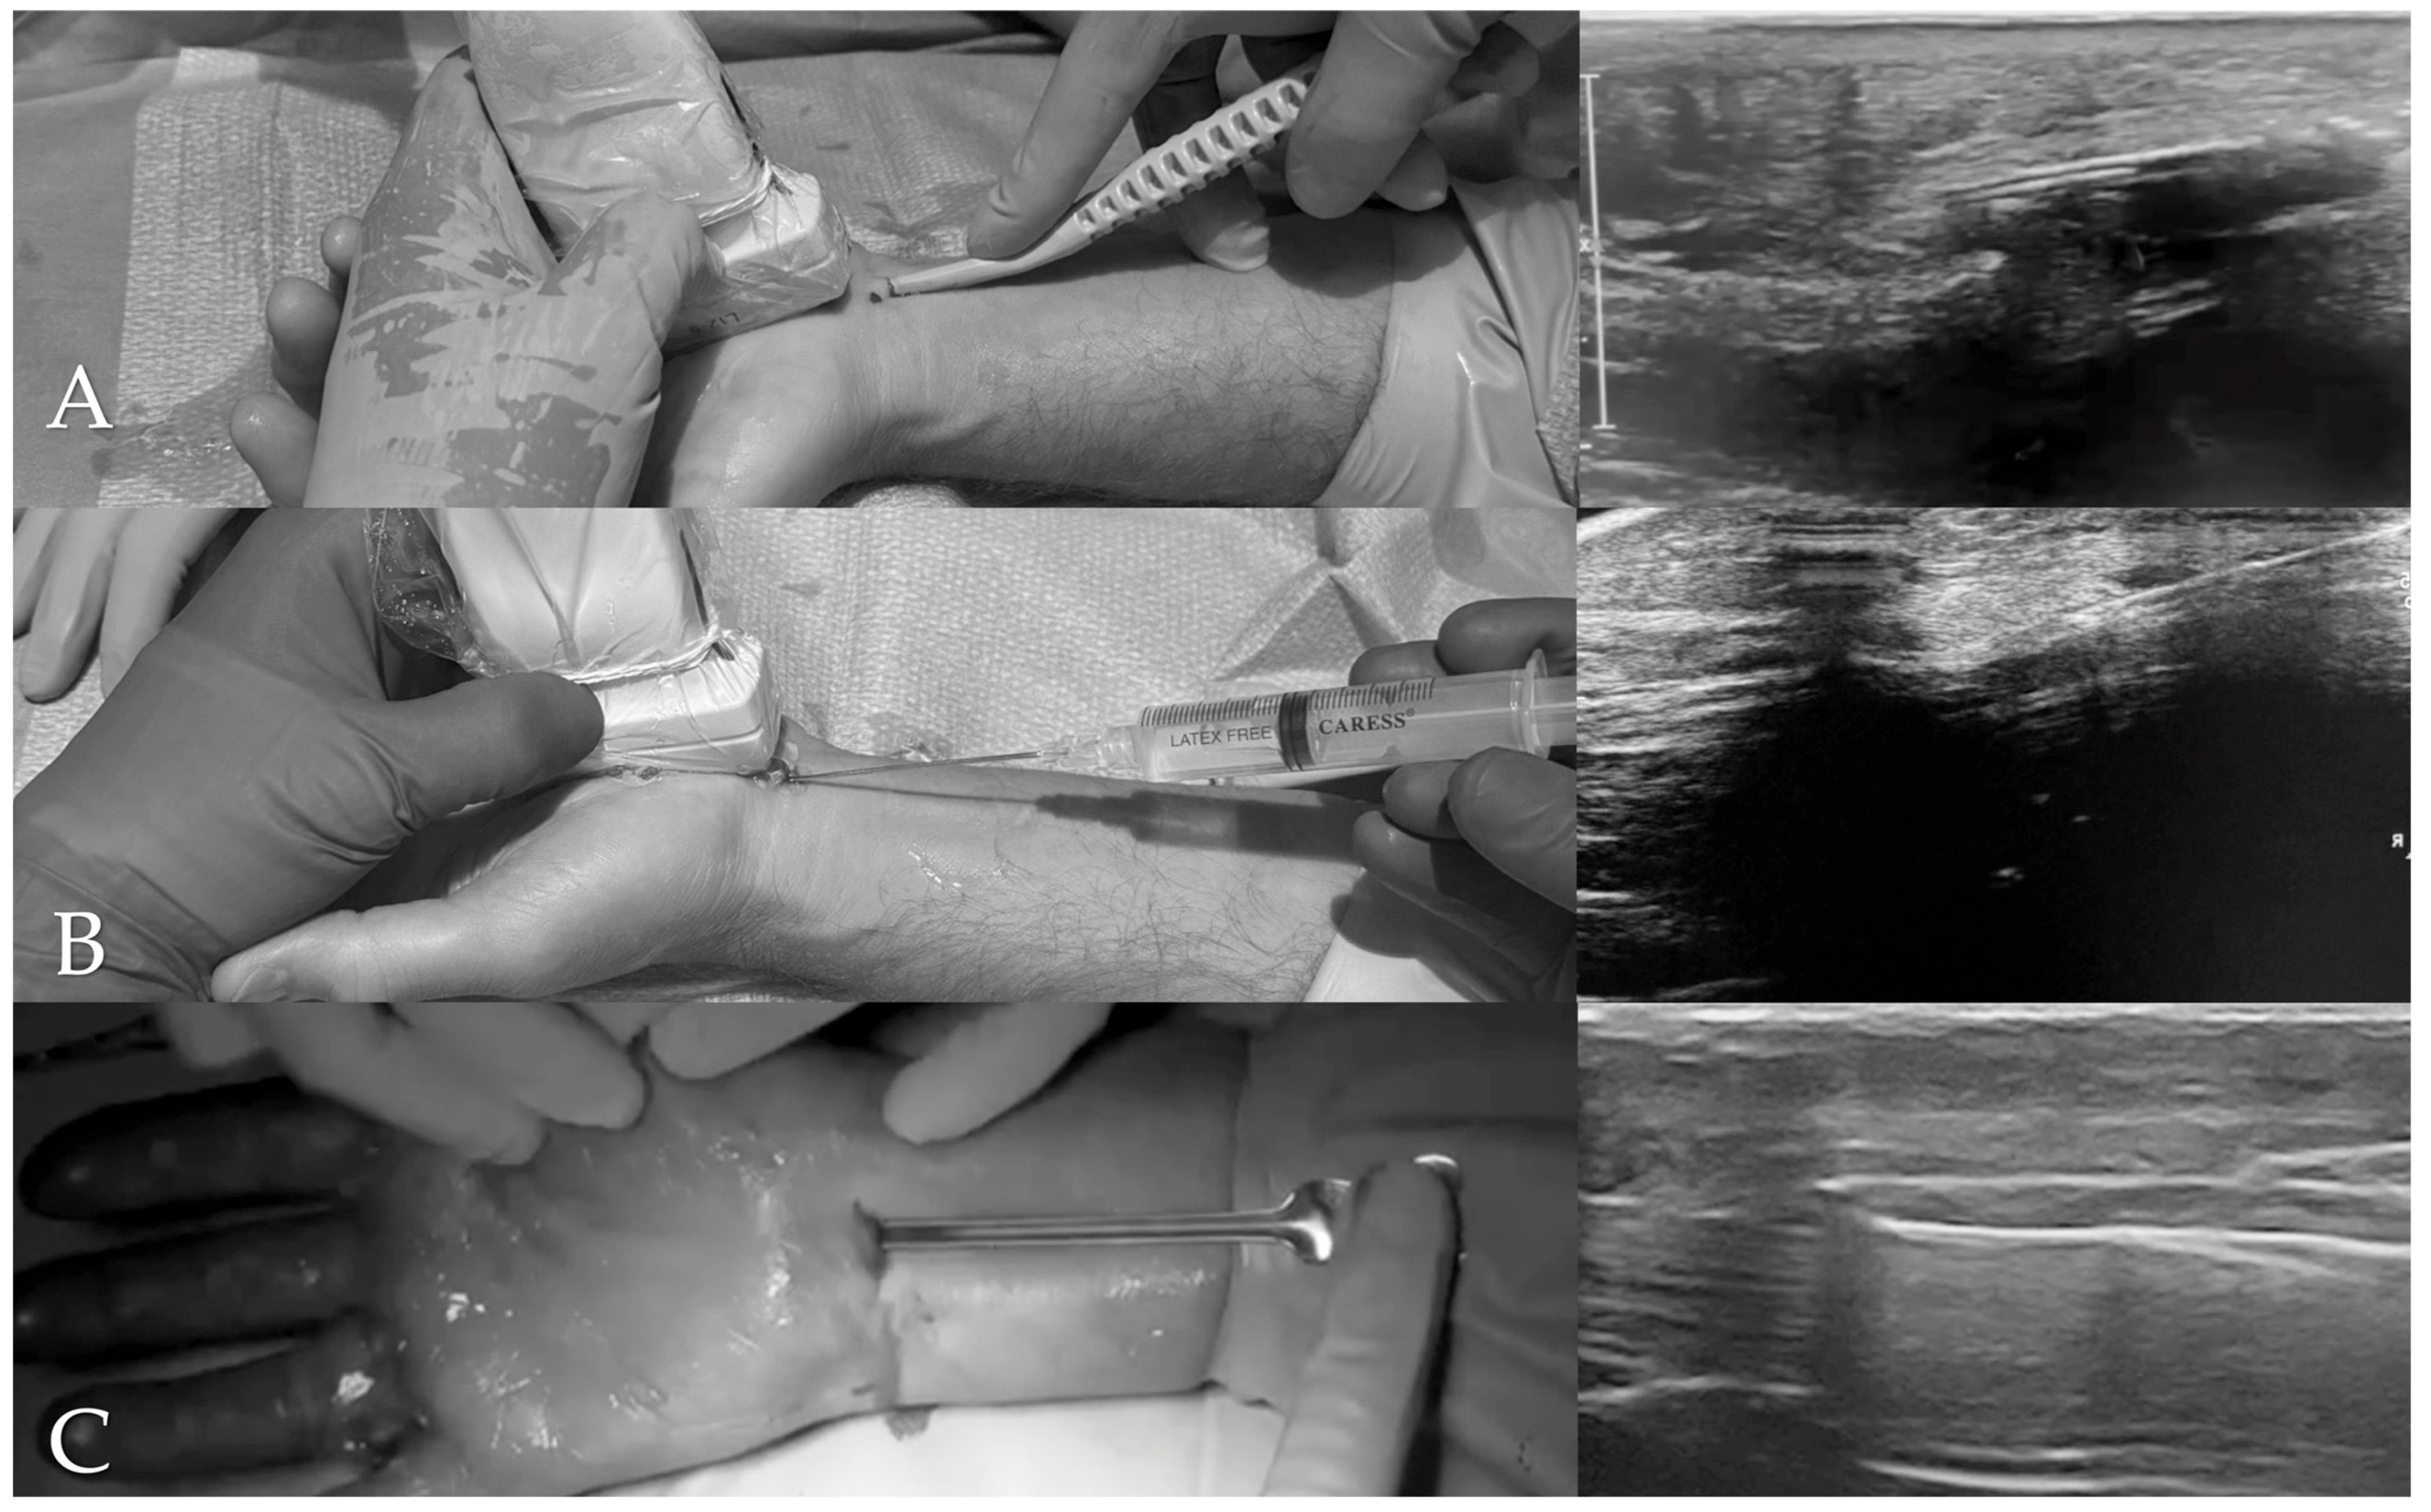

Preoperative ultrasound evaluation showed a mean CSA of the median nerve of 12.81 mm2 (SD: 2.16; range: 6.2–29.2 mm2). At 4 weeks postoperatively, the CSA had decreased to a mean of 8.83 mm2 (SD: 2.24; range: 5.3–26.9 mm2; Figure 3). This change was statistically significant (Wilcoxon signed-rank test W = 3340.0, p < 0.0001).

A significant reduction in the cross-sectional area (CSA) of the median nerve was observed following UGCTR, reflecting the structural efficacy of the procedure: the mean reduction in CSA at 4 weeks was 3.98 mm2, indicating an early and consistent decrease in median nerve swelling after decompression.

These findings are consistent with those reported by Saglam et al., who observed a significant decrease in median nerve CSA following surgical release, using ultrasonography to monitor structural recovery [15].

The reduction in CSA provides an anatomical indicator of successful decompression; however, as current literature has not demonstrated a strong correlation between post-surgical nerve size and clinical symptoms, CSA should not be considered an isolated outcome measure but interpreted together with clinical outcomes.

Figure 3. Cross-sectional area (CSA) of the median nerve before and 4 weeks after surgery.